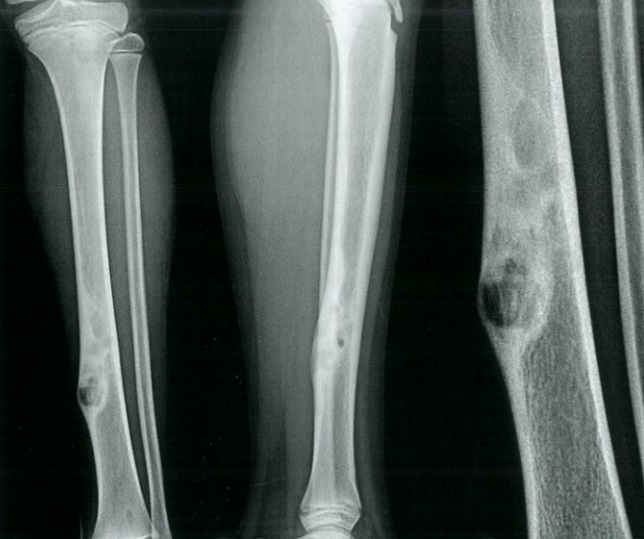

9

Q

Qual diagnóstico?

A

Encondromatose múltipla

Dx: Doença de Ollier

How well did you know this?